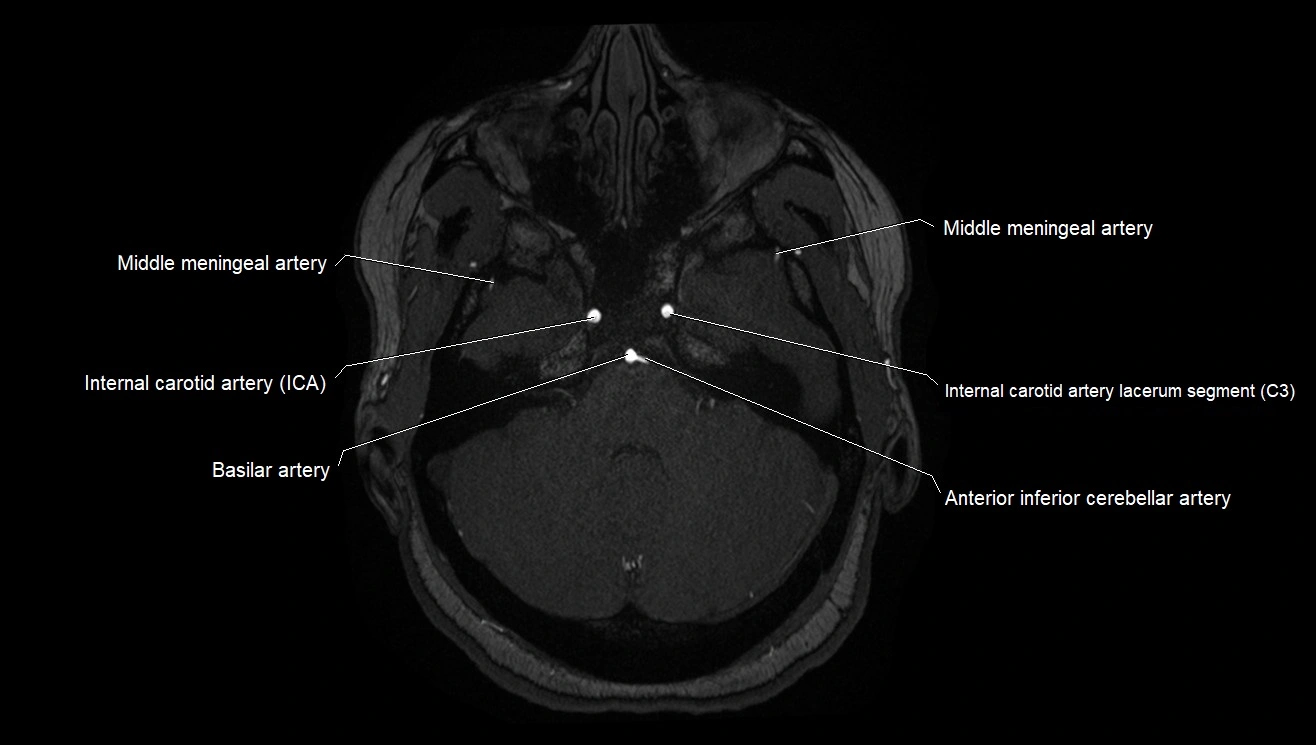

CTA (CT Angiography):

• Opacified with iodinated contrast, AChA appears as a bright high-attenuation vessel

• Visualized from ICA origin along optic tract toward choroid plexus

• 3D reconstructions depict its course and relation to adjacent arteries

• Gold standard for identifying aneurysms, occlusion, or vascular anomalies

CT images

image